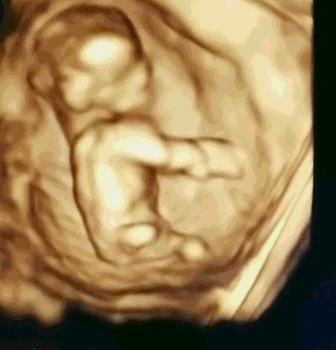

大连美琳达妇儿医院NT检查费用是多少?NT即颈项透明层,指胎儿颈后皮下组织内液体积聚的厚度,反映在超声声像图上,即为胎儿颈椎水平矢状切面上颈后皮肤至皮下软组织之间无回声层的厚度。那么,大连美琳达妇儿医院NT检查费用是多少?

关于价格方面,一般情况下与医院的规模、拥有的医疗设备、看诊的产科医生资历有关。而大连美琳达妇儿医院NT检查,采用的是美国GE高清彩超设备,该设备是目前筛查胎儿畸形的全面设备,可清楚观察胎儿的生长发育情况,完整获取临床超声诊断医学信息,为医生准确诊断提供了有力的科学依据。同时,该设备具有安全辐射小、成像更清晰、数值更精确等特点,因而其检测结果与一般医院普通彩超相比更值得信赖。

NT检查是孕早期排除胎儿异常的必查项目。为了在妊娠较早阶段诊断染色体疾病和发现多种原因造成的胎儿异常,所有孕妈咪们都应该积极地做好检查,以保证宝宝的顺利诞生。而NT检查最好在怀孕11~14周做,超过14周检查会不准确。